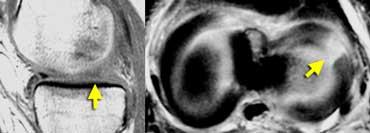

TRÁI: chân bám sụn chêm trong bình thường nằm ngay phía trước dây chằng chéo sau. PHẢI: mất chân bám sừng sau do rách chân bám sụn chêm.

Chân bám sừng sau nằm ngay phía trước dây chằng chéo sau.

Nếu không thấy chân bám này trên các lát cắt sagittal, cần nghĩ đến rách chân bám sụn chêm (hình minh họa).